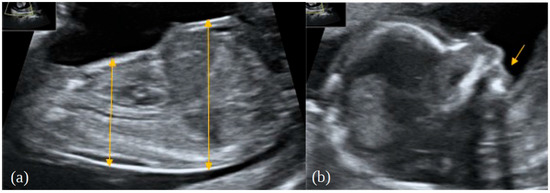

2. Case Report